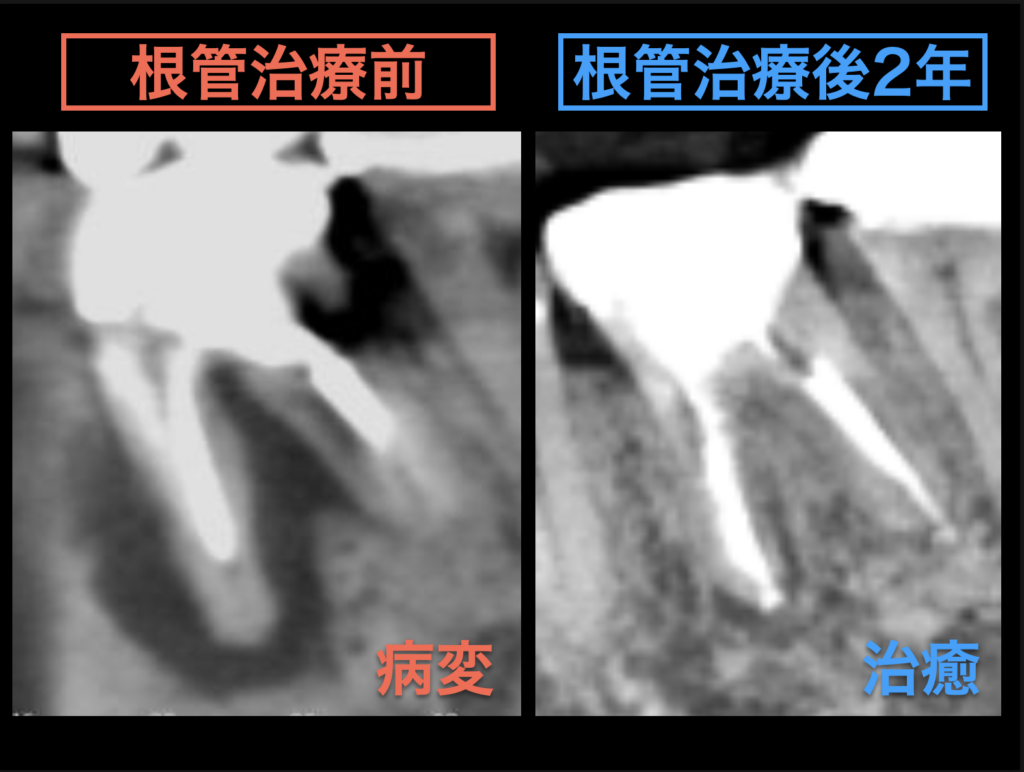

よくレントゲンに写った根の先の病変の大きさだけを見て、「これは治る・治らない」「抜歯する・抜歯しない」と判断されることが多いのですが、本当にそうなのでしょうか?

確かに根の先の病変の大きさが治療の成否に影響する可能性はあるのですが、それが全てではありません。

病変の大きさが大きくても、明らかに感染源が残っていると考えられるようなケースや根の中が大量に細菌に汚染されているようなケースでは、それらをしっかりと消毒することで病変が治る場合もあります。